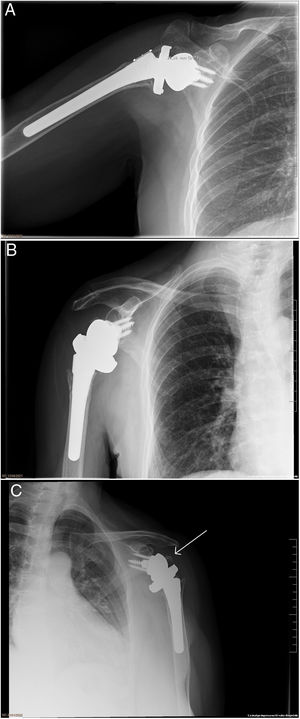

Postoperatoriamente, se realizaron controles al mes, 3 meses, 6 meses y al año. Dos cirujanos independientes fueron los encargados de valorar inicialmente la correcta consolidación de las tuberosidades, y posteriormente era corroborado por un cirujano sénior en las 2 proyecciones radiográficas (AP verdadera y axial) a todos los pacientes que decidieron participar y llevaban como mÃnimo un año de seguimiento. Se categorizó como consolidación no anatómica (grupo 2) cuando existÃa: no unión, malunión u osteólisis de las tuberosidades. Más especÃficamente, dentro del subgrupo se incluyeron: los pacientes con ausencia de tuberosidad, una separación>1cm del fragmento a la diáfisis humeral, o que la tuberosidad se encontrase por encima de la bandeja humeral (figs. 1 y 2). El estudio fue aprobado por el Comité Ético de Investigación.

En este estudio, se obtuvo una baja tasa de consolidación de las tuberosidades (54%), ligeramente inferior a la descrita en la literatura (64-84%)16–23; solo Chun et al.24 reportan una tasa de consolidación inferior (34%)24. Esta diferencia, según nuestra hipótesis inicial, puede ser debida al diseño protésico utilizado: diseño lateralizado con bandeja de diámetro grande, siendo el tamaño más pequeño disponible el de 44mm. Este gran diámetro puede dificultar el cierre de las tuberosidades, quedando estas con excesiva tensión y comprometiendo asà la consolidación cuando se compara con los otros diseños protésicos (fig. 3). Esta diferencia de tamaño en la bandeja es notable si tenemos en cuenta el incremento de área de superficie que supone. Por ejemplo, la diferencia de superficie (cm2) entre la bandeja de 32mm de Humelock Reversed® (área de superficie 8cm2), de Fx Shoulder Solutions, y la bandeja de 44mm (área de superficie 15,2cm2) modelo Comprehensive® Reverse Shoulder System, de Zimmer Biomet, corresponde a un aumento de un 90% (tabla 4).